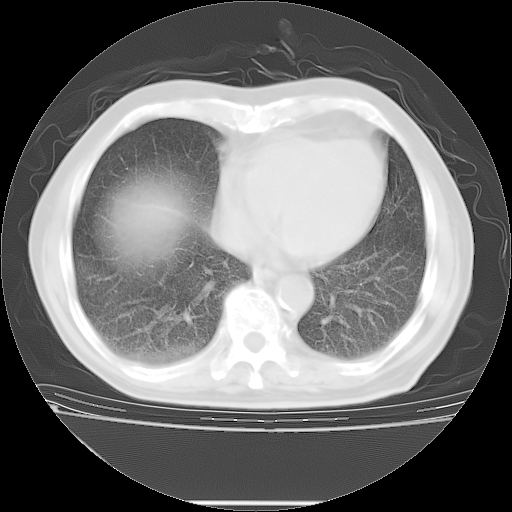

今天复查肺部CT,发现双肺广泛磨玻璃样改变。所以我把3月19日和5月9日相隔50天的肺部CT上传。请大家会诊。

5月9日肺部CT(在4月27日齐鲁医院肺部CT描述部分肺组织磨玻璃样改变,12天后肺组织广泛磨玻璃样改变)

大致读了系列胸部CT:纵隔窗无明显异常,肺窗:从4、27至今:主要是双肺中下野外带可见毛玻璃样改变,目前处于急性肺泡炎阶段,至于原因考虑1、结替组织或胶原血管性疾病所致?2、恶性疾病如恶组在肺部所致的表现或细支气管肺泡癌?3、药物或其它原因如肺蛋白沉着症所致肺泡炎目前不太可能?总之,明天就去请我院的呼吸科、感染科、血液科和临免专家会诊哈。